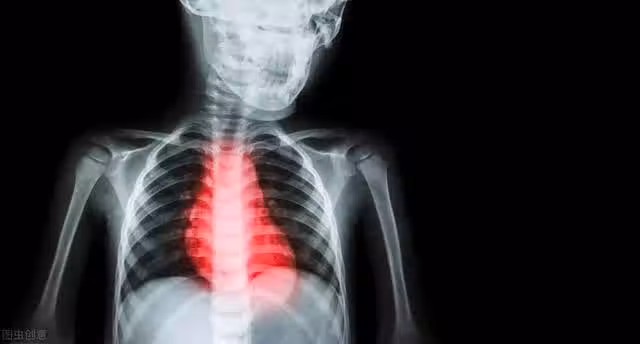

心肌梗死也即冠狀動脈急性、持續性缺血血氧所引起的心肌壞死。我們都知道心臟就像一個"水泵",推動血液在血管中循環流動,維持器官的正常代謝和功能。

但心臟肌肉本身也是需要血液供應才能正常運轉的。冠狀動脈便是專為心肌供血的"糧道"。

由於三高等原因,在這個"糧道"四周的牆壁上,可能存在著一些因膽固醇等脂質沉積而形成的脂質斑塊,全稱動脈粥樣硬化性斑塊。

在平時,這些斑塊雖部分堵塞住了血管,但依然能夠維持心肌供血。

一旦在熬夜、情緒激動、劇烈運動、受到寒冷刺激等因素刺激下,血管收縮或者心肌跳動頻率加快,就會導致心肌供血不足。

突發的心肌缺血會造成心臟無法適應突如其來的代謝紊亂,進一步引發惡性心率失常,比如室顫。

此時如果沒有得到及時的心肺復甦,或者復甦失敗了,心臟徹底失去泵血功能,血液循環停止。

器官失去營養供給的動力來源,無法正常工作,於是就會猝死。